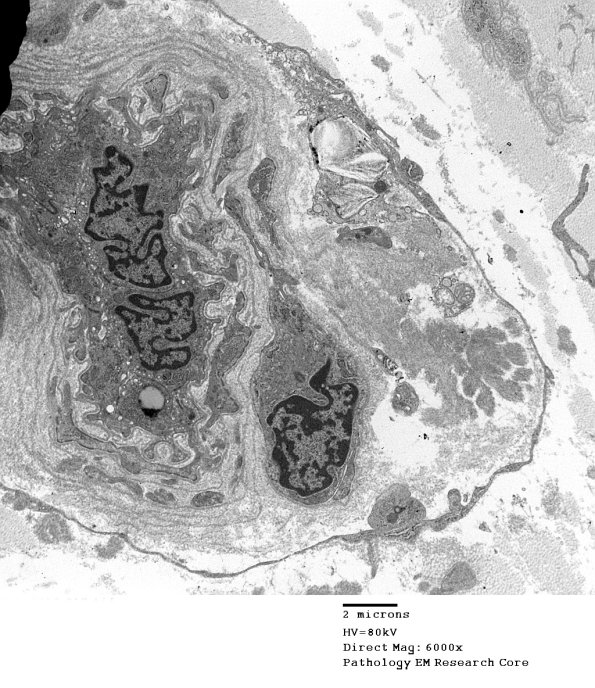

8D4,5 The asymmetric appearance of this vessel is contributed by amyloid fibrils. (electron micrographs)